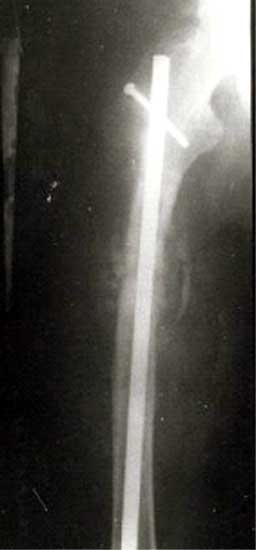

股骨近段骨折,钢板、外固定后失败。改用带锁髓内钉固定,4个月后骨折愈合